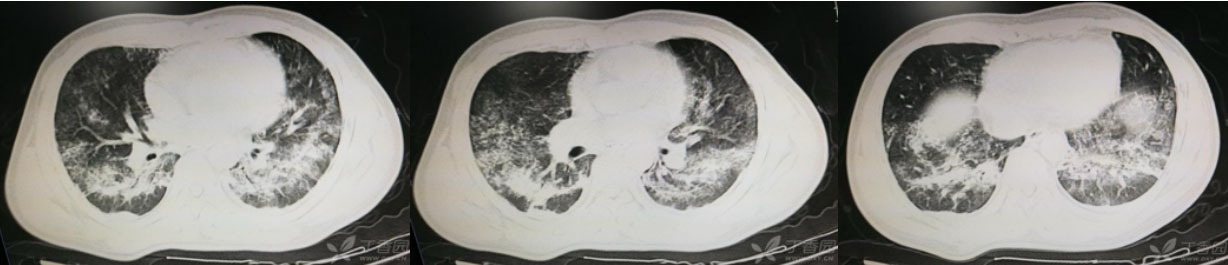

影像学检查:胸部X线、CT等,以观察肺部炎症和胸腔积液情况。

经过一个疗程的治疗,苏某的病情得到了明显的改善,肺部炎症得到控制,胸腔积液量明显减少,气急等症状也有所缓解。